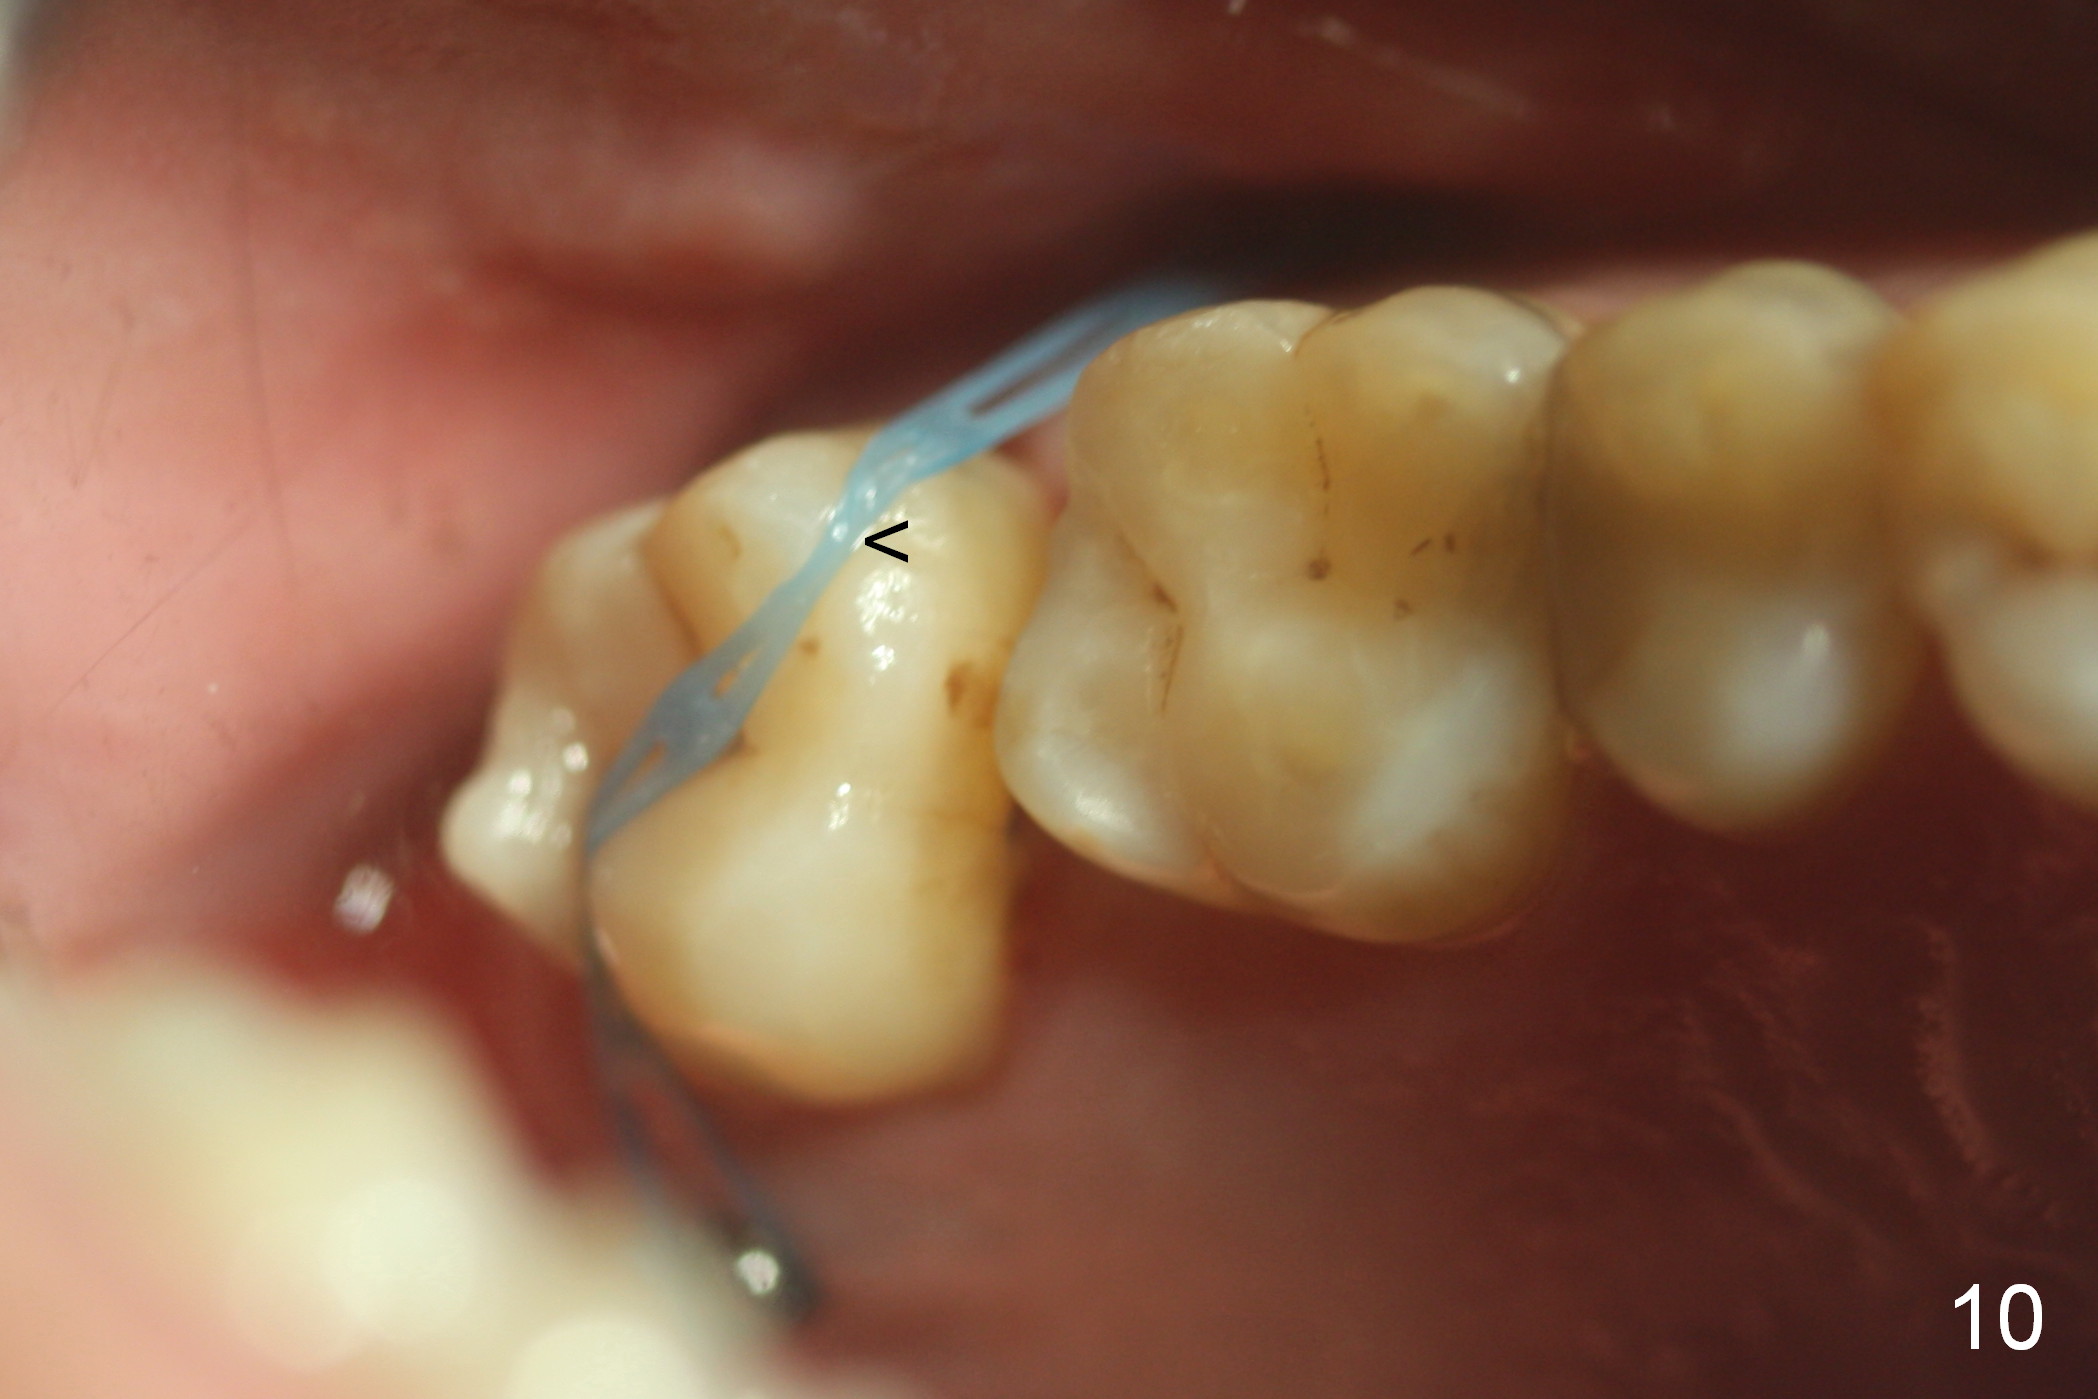

Four months post intrusion, the tooth #15 is distalized instead (Fig.9 arrow). To facilitate mesialization, the power chain is engaged into the mesiobuccal slot (Fig.10 <). It is 1 month after the change in position of the power chain. Has the tooth mesialized? Regional orthodontic devices are placed, but the patient is not cooperative, refusing any intrusion treatment. Prosthetic intrusion will be tried once the implant at #18 osteointegrates.